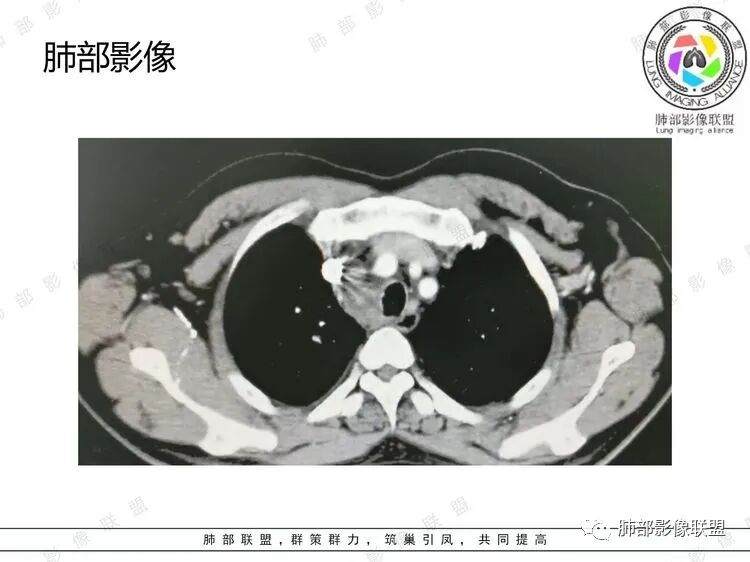

男,51岁,气促一月,发热半月,既往高血压病史及长期吸烟史。CT示右肺上叶沿支气管血管束分布多发小结节,叶间胸膜亦见,支气管壁增厚。纵隔、右肺门、膈上前组、腹膜后多发肿大淋巴结,部分融合成团,隆突下融合淋巴结内似见血管影,增强扫描轻度强化,胸腔积液及心包积液。综合考虑为淋巴瘤可能

B超:腹膜后淋巴结肿大。胸部CT:纵隔、右肺门多发肿大淋巴结,部分融合呈团块状,纵隔淋巴结有坏死,右肺多发中轴间质增厚及小叶间隔增厚,部分实变,沿支气管血管束分布有多发粟粒结节影,右侧胸腔积液,心包积液。

男,51岁,气促一月,发热半月。既往高血压、长期吸烟史。腹部B超示腹膜后淋巴结多发肿大。CT示:肺气肿、刀鞘样气管,肺动脉增粗,右肺动脉受周围肿大融合淋巴结压迫,右肺上叶沿支气管血管束分布多发小结节,叶间胸膜亦见,支气管壁增厚,右中间支气管可见结节样隆起。纵隔(内乳动脉旁淋巴结肿大)多发、右肺门多发肿大淋巴结,部分融合,隆突下融合淋巴结内似见血管影,增强扫描轻度强化,右侧胸腔积液及心包积液。综合考虑:恶性病灶,淋巴瘤?小细胞?